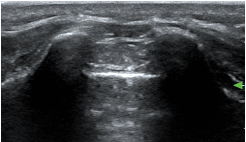

Sonoanatomy

Ultrasound probe selection: linear high frequency probe

Mapping/scout scan: look between the intervertebral spinous processes and laminae:

1)Probe position transverse over the sacral cornua (-> frog’s eyes US view)

2)Then rotate probe 90 degrees for a longitudinal view

Identify:

•Sacral cornua

•Sacrum

•Sacrococcygeal membrane

•End of the dural sac (hyperechoic (<-> CSF are anechoic (black)

•Caudal epidural space

•Assess the position of the dural sac in relation to the sacrococcygeal membrane

NOTE: Ultrasound can't see through bone; so with increasing age (= increasing angulation of the spinous processes and increasing ossification of the laminae) the size of the echo window will diminish -> you might need to scan paramedian

TIP: use a large linear probe (50mm) – this will allow you to visualise more vertebrae in one image for easier monitoring of needle approach and LA spread